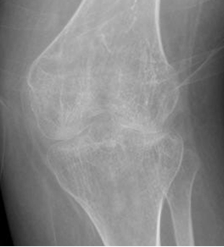

Aparte de los signos clásicos de AR, en este grupo de pacientes hay reacción perióstica en la diáfisis de los metacarpianos y falanges proximales, anquilosis interfalángicas y de la columna vertebral y alteración en el crecimiento. (2). Es clásico el crecimiento anormal, en los cóndilos mediales de la rodilla. (2).